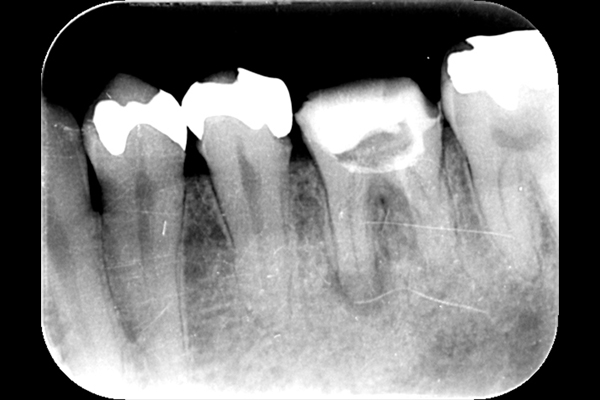

歯の根の治療は難しいことは先述しましたが、歯の内部からの治療だけでは治らないことがあります。

それは歯の先に枝分かれが多く存在し、そこにばい菌が入り込んで難治性となっているからです。ではその場合どうするのか?外科治療をします。その枝分かれの部分を切り落とすのです。今回はその前後のレントゲンの写真をお見せします。

| 根の中の薬が十分に充填されておらず、根の先が周りと比べて黒くなっており、炎症があると判断できます。 | 根の中にしっかりとお薬を緊密に充填しましたが、まだ根の先に黒くなっている部分があります。 |